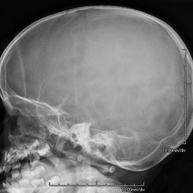

- RX Cráneo

Técnica mediante la cual, utilizando rayos X, se obtienen imágenes del cráneo para su estudio. Indicaciones: traumatismo, cierre precoz de suturas craneales.